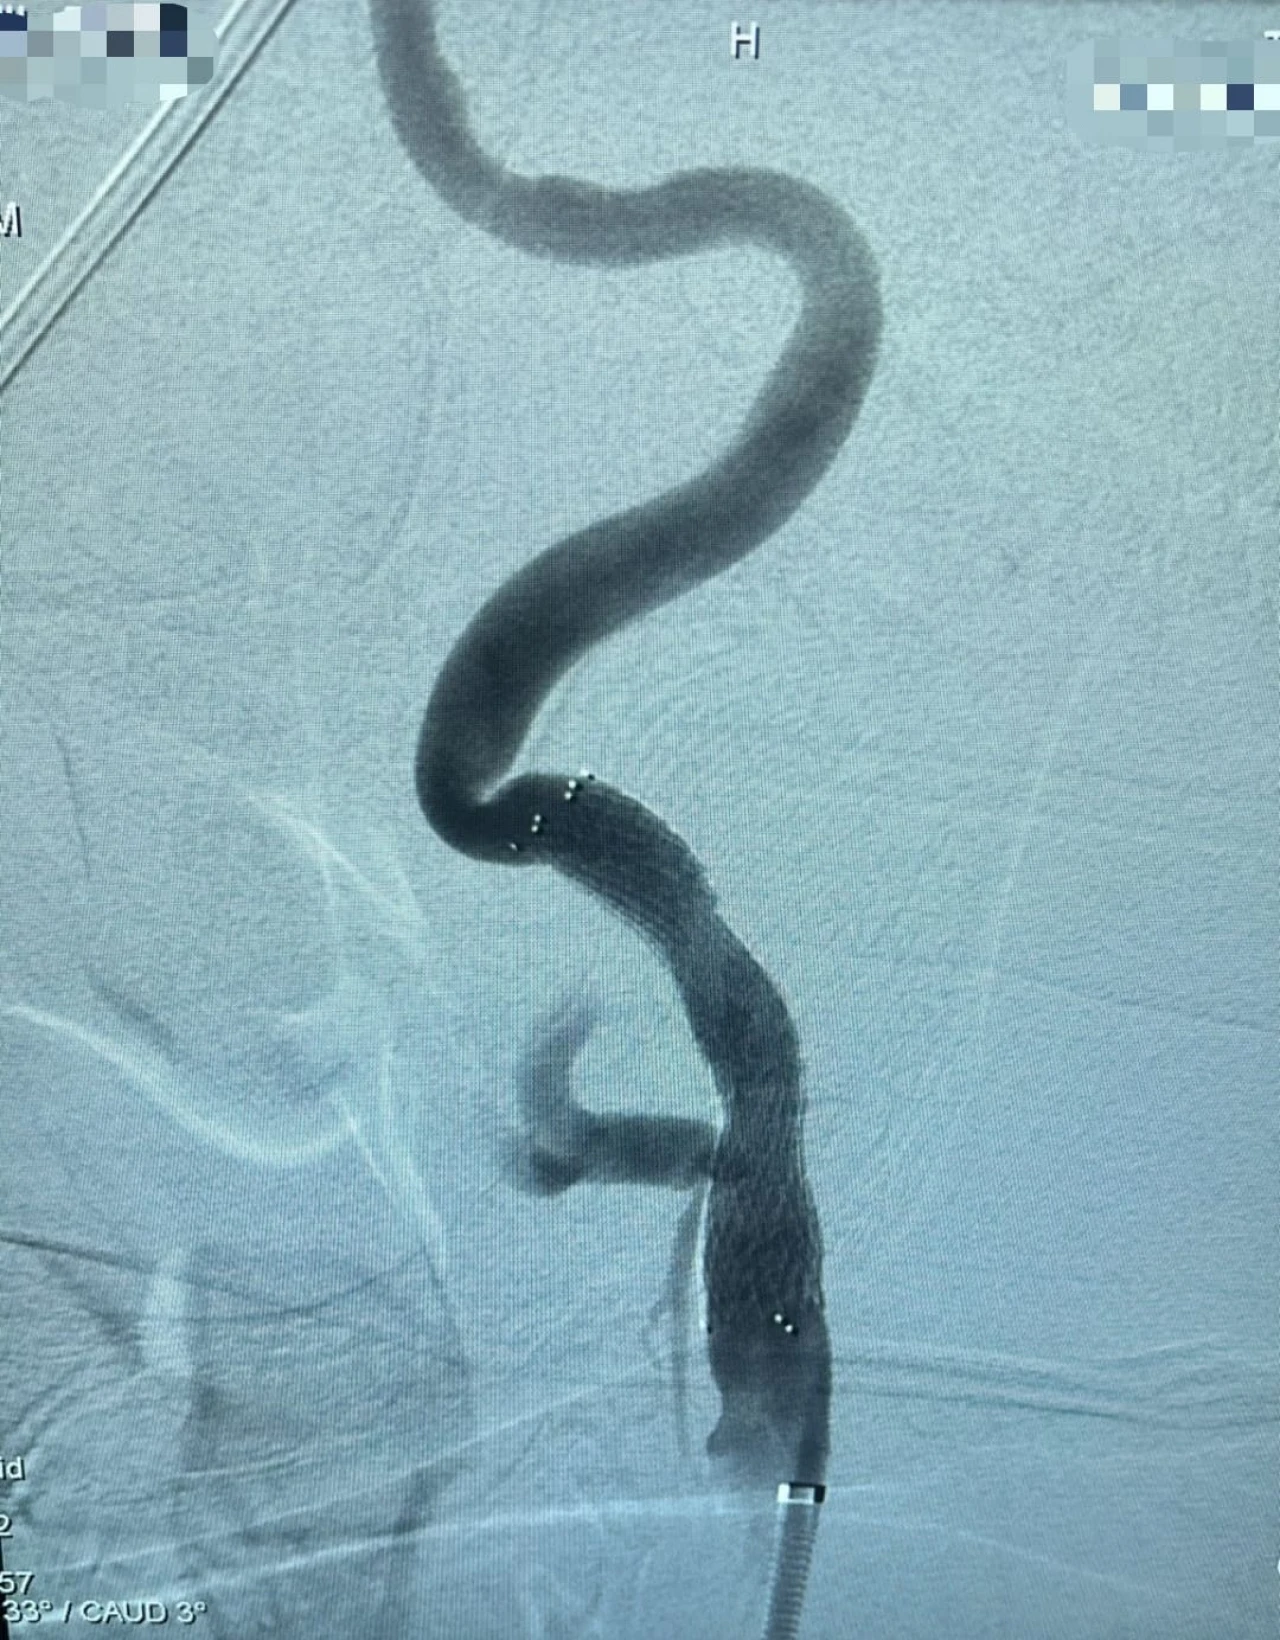

Şah damarında tespit edilen darlık, özel bir balonla genişletilir ve ardından stent adı verilen ince bir metal kafes yerleştirilerek damarın açık kalması sağlanır. Bu sayede kan akışı normale döner ve felç geçirme riski önemli ölçüde azalır. İşlem, ameliyat gerektirmeden anjiyografi ünitesinde yapılır.

Girişimsel Radyoloji Uzmanı Dr. Öğretim Üyesi İsmail Taşkent, “Şah damarı darlıkları felç riskinin en önemli nedenlerinden biridir. Bu müdahale artık hastanemizde güvenli ve etkili şekilde uygulanıyor. Böylece hastalarımız şehir dışına gitmeden, bu önemli tedaviye burada ulaşabiliyor” dedi.